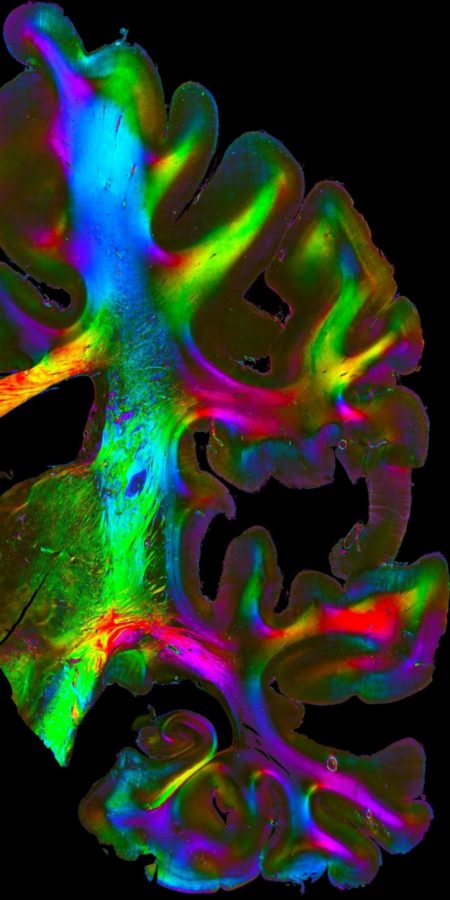

Ein dreidimensionaler Gehirnatlas sowie verschiedene Methoden der Hirnsimulation und Modellierung finden sich ebenfalls hier. Ein in Jülich speziell entwickeltes Verfahren, das mit polarisiertem Licht arbeitet, ist dadurch in der Lage, die hauchdünnen Nervenendigungen sichtbar zu machen. Bilder dieser bunt gefärbten Axone wurden auf große Poster gezogen.